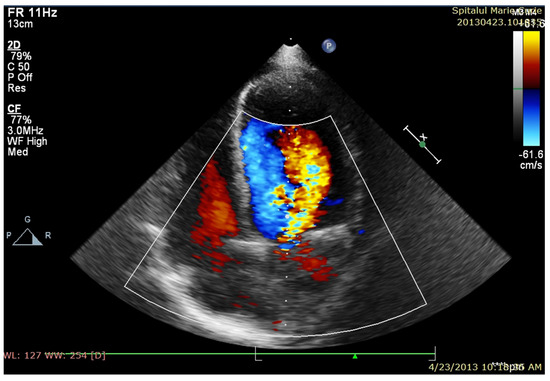

After four days of admission, vesper fever (38.2 C) progressively recurred, and the biological inflammatory syndrome slowly developed. Management was changed to Meropenem at 100 mg/kg/day and Linezolid at 25 mg/kg/day (Vancomycin was replaced with Linezolid due to a severe allergic reaction after the second administration), and this was continued for six weeks. In the first week of treatment, the patient started to develop a significant new diastolic murmur, and echocardiography confirmed spontaneous drainage of the perivalvular aortic abscess, resulting in severe aortic insufficiency and dilation of the left aortic coronary sinus (Figure 1a,b), along with a decrease in LVEF (45%).

Figure 1. (a) TTE PLAX—paravalvular aortic abscess—in the course of formation; (b) after spontaneous evacuation.